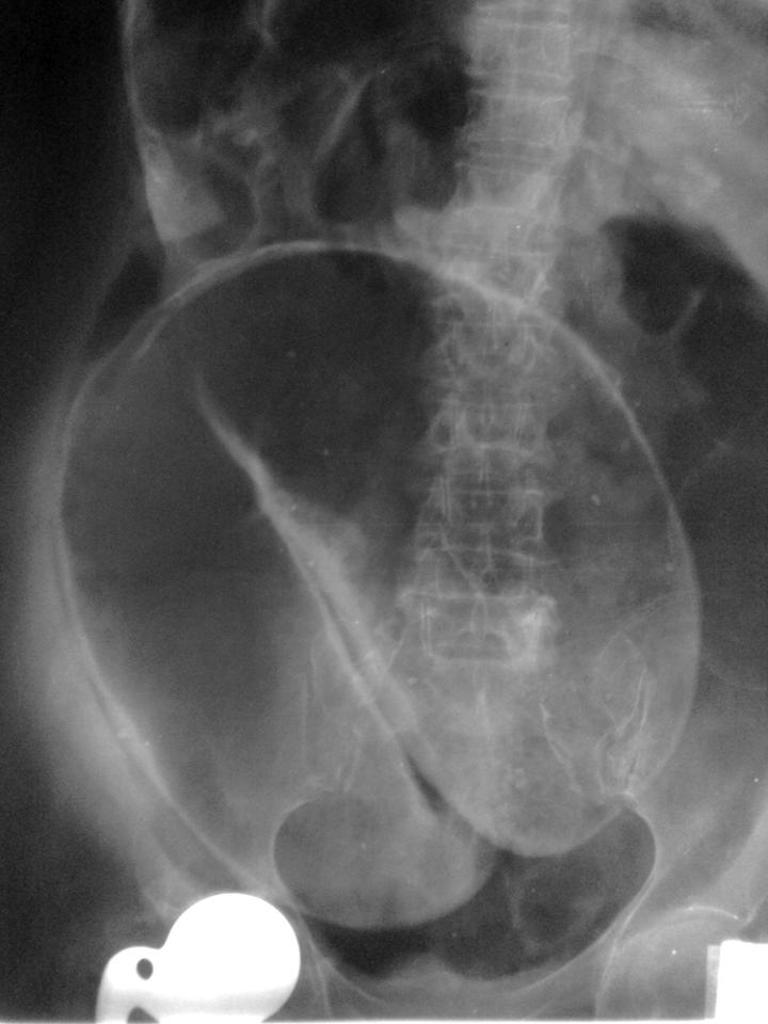

what is this condition

TOXIC MEGACOLON (acute deterioration of UC):